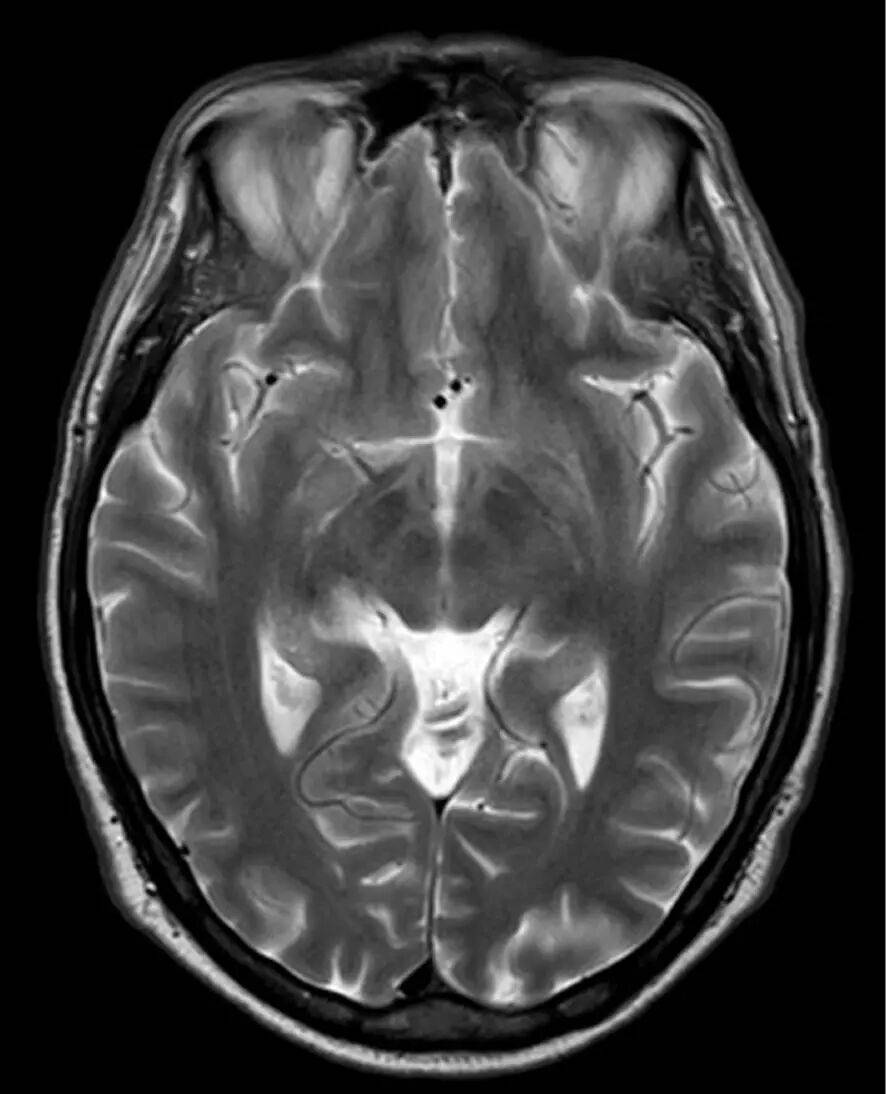

图1 头颅MRI显示双侧小脑区软脑膜-小静脉轻度强化 研究意义 本研究发现精神运动性激越可作为TOSV神经侵袭性感染的突出特征,修正了传统认为该病毒仅引起轻度脑膜炎的认知。病例中出现的攻击性行为改变、幻觉等精神症状,提示病毒可能特异性影响边缘系统功能。这一发现对临床实践具有重要启示:在夏季地中海地区就诊的急性器质性精神综合征患者中,需将TOSV纳入鉴别诊断范围,尤其当患者有白蛉接触史时。从公共卫生角度看,研究结果强调需加强流行区医疗机构的病原体快速检测能力,从而避免误诊为原发性精神疾病而延误抗病毒治疗。病毒神经嗜性机制的研究缺口也值得关注,未来需开展宿主-病原体互作研究,阐明病毒株特异性与临床表现多样性的关联。 Please cite this article as 引用信息 Citation: |